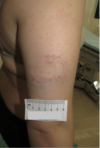

Beskriv læsionerne på billedet nedenfor. Derefter angiv alder for læsionen og traumemekanismen med eventuelt våben

På højre underarms strækkeside, i et område målende 6 x11 cm, beliggende 1 cm under albuens spids, to friske hudafskrabninger, den ene målende 0,5 x1 cm, den anden målende 0,6 x 2 cm med omkringliggende rødviolet blodunderløbent mærke målende 4,5 x6 cm.

Læsionerne skuldes stump vold og kan være opstået ved fald mod genstand eller slag med genstand. I denne case er det slag med et koben!